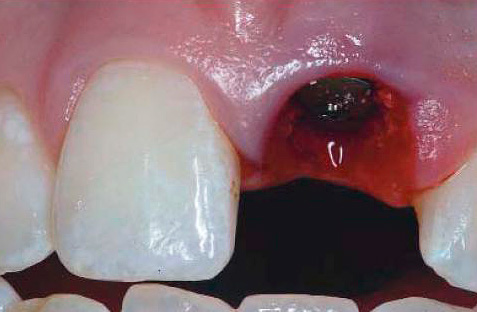

A foto mostra como fica o buraco após a extração do dente após 3 semanas:

Se o processo não é complicado por alveolite, geralmente cerca de 7 dias após a extração do dente, o tecido de granulação substitui quase completamente o coágulo sanguíneo e um osso jovem é formado ativamente. Quanto tempo o orifício crescerá após a extração do dente, para que uma gengiva lisa se forme completamente, depende da natureza da intervenção. Quanto mais grossa a remoção e mais danificados os tecidos circundantes, mais tempo a ferida cicatrizará.